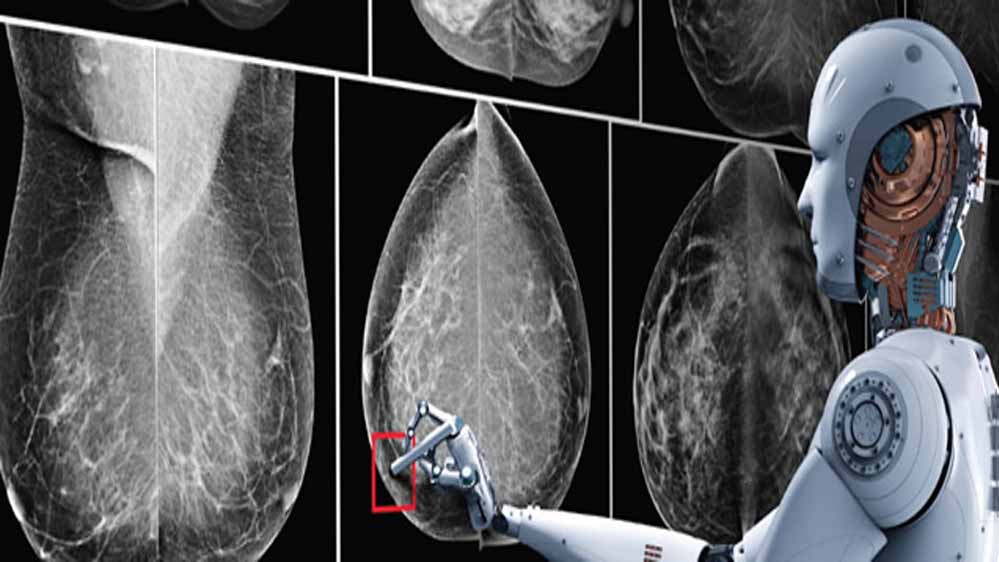

AI से डिटेक्ट करेगा ब्रेस्ट कैंसर

हाल ही में अमेरिका की Duke University के रिसर्चर ने एक New AI डेवलप किया है। इसके रिसर्चर ने दावा किया है कि, AI ब्रेस्ट कैंसर को उसके डेवलप होने से लगभग पांच साल पहले ही डिटेक्ट कर सकता है। अब आनंद महिंद्रा ने साइंस न्यूज नाम के हैंडल पर की गई पोस्ट को रिपोस्ट किया है। उन्होंने इस पर लिखा है कि यह बहुत काम का साबित हो सकता है।

कैंसर का पता लगाने के लिए फिलहाल Biopsies, Microscopic Histological एग्जामिनेशन मेथड का इस्तेमाल किया जाता है। इसके अलावा इमेजिंग टेक्नोलॉजी जैसे MRI, CT स्कैन और PET स्कैन हैं। अब रिसर्चर्स ने दावा किया है कि AI की मदद से एक्यूरेसी के साथ कैंसर की रिपोर्ट दे सकता है।

हाल ही में अमेरिका बेस्ड Duke University के रिसर्चर ने एक New AI डेवलप किया है. यह AI मॉडल कैंसर डेवलप होने से करीब 5 साल पहले कैंसर को बता देगा. ये दावा रिसर्चर ने किया है.

कैंसर का पता लगाने के लिए, जो ट्रेडिशनल तरीका है, वो Biopsies, Microscopic Histological एग्जामिनेशन है. इसके अलावा इमेजिंग टेक्नोलॉजी जैसे MRI, CT और PET Scans हैं. वहीं, AI सिर्फ मेडिकल इमेज को एनालाइज करके ज्यादा बेहतर एक्युरेसी के साथ कैंसर की रिपोर्ट दे सकता है, जो दावा रिसर्चर ने किया है.